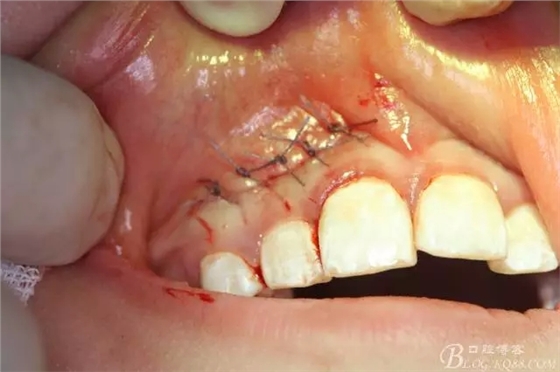

病例資料: 患者、柴xx、女、16歲。??茩z查及病歷如下圖: 患者同意我院正畸科建議,遂轉(zhuǎn)診倒外科。術(shù)前簽知情同意書。 治療過程: 圖1.術(shù)前的CBCT檢查:13阻生,疑為含牙囊腫。縱剖面顯示12牙根吸收至根尖1/3。 圖2.局部麻醉下 。行唇側(cè)弧形切口,12松動不到1°。 圖3.翻瓣、暴露骨面。 圖4.去骨、 暴露13牙冠 圖5.去骨、逐漸顯露13。 圖7.拔除13. 圖8.摘除囊壁 圖9.必須完整剝離囊壁。 圖10.摘除囊壁后形成的骨腔 圖11.超聲骨刀12根尖倒預(yù)備 圖13. 消毒棉球骨腔內(nèi)隔濕血液,紙尖干燥倒預(yù)備好的根管 圖14. 紙尖無血即可 圖15。MTA倒充填 圖16.骨腔填塞膠原蛋白海綿 圖17.拔除的13及摘除的囊壁 圖18.縫合 圖19.術(shù)后x線根尖片影像:MTA封閉根尖